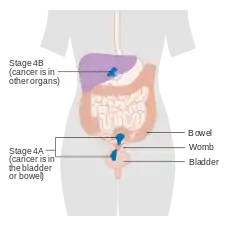

Staging

Endometrial carcinoma is surgically staged using the FIGO cancer staging system. The 2009 FIGO staging system is as follows:[63][64]

| Stage | Description |

|---|---|

| IA | Tumor is confined to the uterus with less than half myometrial invasion |

| IB | Tumor is confined to the uterus with more than half myometrial invasion |

| II | Tumor involves the uterus and the cervical stroma |

| IIIA | Tumor invades serosa or adnexa |

| IIIB | Vaginal and/or parametrial involvement |

| IIIC1 | Pelvic lymph node involvement |

| IIIC2 | Para-aortic lymph node involvement, with or without pelvic node involvement |

| IVA | Tumor invades bladder mucosa and/or bowel mucosa |

| IVB | Distant metastases including abdominal metastases and/or inguinal lymph nodes |

Myometrial invasion and involvement of the pelvic and para-aortic lymph nodes are the most commonly seen patterns of spread.[2] A Stage 0 is sometimes included, in this case it is referred to as "carcinoma in situ".[9] In 26% of presumably early-stage cancers, intraoperative staging revealed pelvic and distant metastases, making comprehensive surgical staging necessary.[27]

Stage IA and IB endometrial cancer

Stage IA and IB endometrial cancer Stage II endometrial cancer

Stage II endometrial cancer Stage III endometrial cancer

Stage III endometrial cancer Stage IV endometrial cancer

Stage IV endometrial cancer